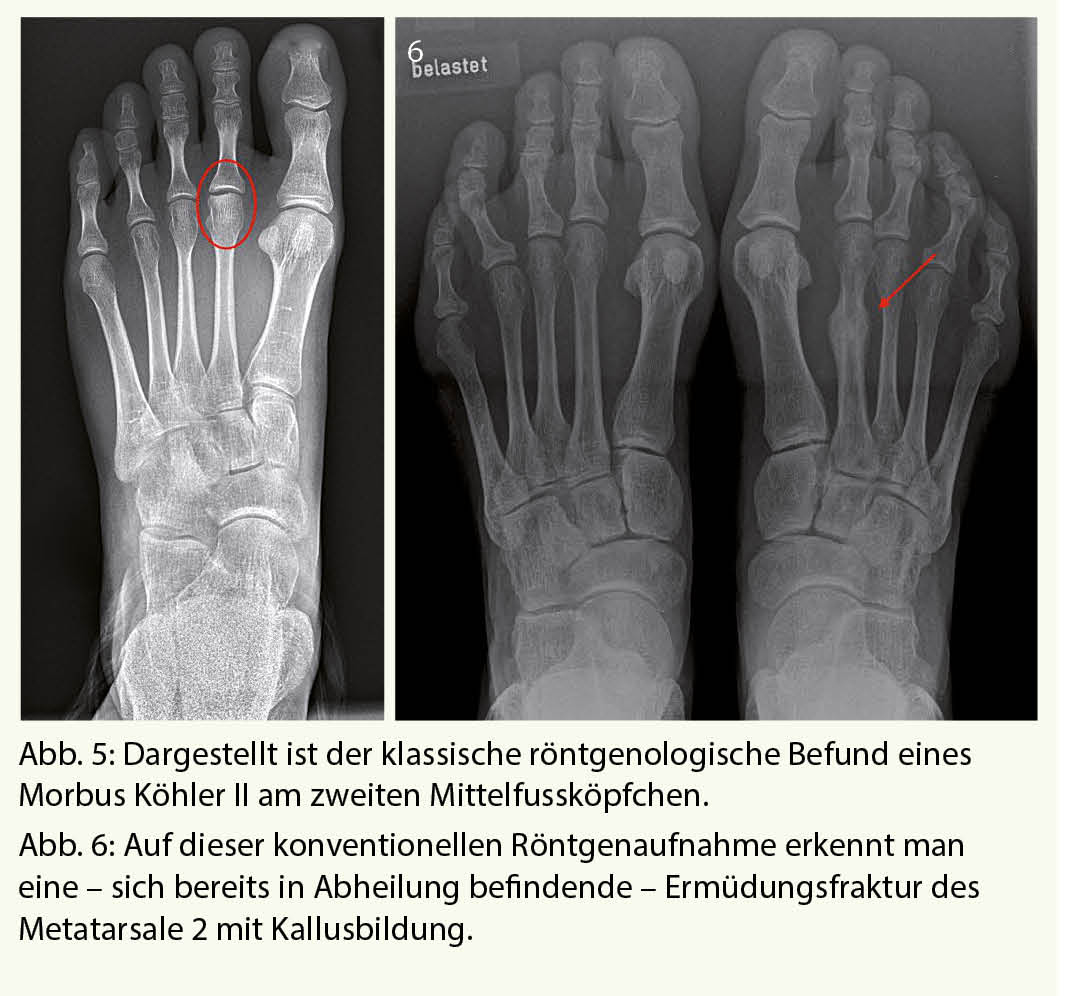

Röntgenaufnahmen unter Belastung gehören zur Standarduntersuchung eines jeden schmerzhaften Vorfusses. Pathologien an den Mittelfussköpfchen oder Ermüdungsfrakturen können hiermit in der Regel zufriedenstellend diagnostiziert werden (Abb. 5 und 6). Dabei muss jedoch beachtet werden, dass Ermüdungsfrakturen oft erst 2-3 Wochen nach Schmerzbeginn anhand der beginnenden Kallusbildung sichtbar werden.

Ermüdungsfrakturen

Ermüdungsfrakturen entstehen in Folge einer dauerhaften Überbelastung des Knochens. In der Regel sind hiervon sportlich aktive Menschen betroffen, welche wöchentlich eine hohe Belastung auf sich nehmen – insbesondere Läufer. Das überbeanspruchte Gewebe erhält nicht genügend Zeit zur Regeneration, anatomische Skelettvarianten mit daraus resultierender Fehlbelastung des Fusses unterstützen diesen Prozess.

Eine Sonderform stellen die sogenannten pathologischen Frakturen dar, welche durch eine vorbestehende Schwächung des Knochens verursacht werden – durch die Einnahme von Medikamenten, im Rahmen tumoröser Erkrankungen oder als Folge der natürlichen Knochendichteminderung im Alter.